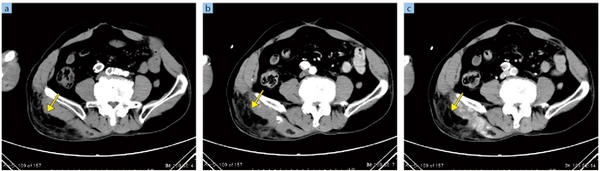

同センターでは,フィリップスの金属アーチファクトを低減する再構成技術であるO-MAR(Metal Artifact Reduction for Orthopedic Implant)を導入し,整形外科の人工股関節が留置された患者さんへの撮影などに活用している。O-MARは,独自のアルゴリズムによって整形用の金属インプラントのアーチファクトを補正する逐次近似再構成を応用した技術で,チェックボックスをクリックするだけで使用でき,撮影後にraw dataを元に適用することも可能だ。データとしては,オリジナル画像とO-MAR適用画像の2種類が作成され,両画像を比較して観察することが推奨されている。

「整形外科領域ではもちろんのこと,大腿骨骨頭置換術によって人工股関節のようなインプラントが入っている患者さんに対して,検査時にO-MARを適用することで金属アーチファクトが除去され,関節周囲や膀胱,前立腺などの軟部組織の観察がある程度可能になります。画面上でO-MAR適用のチェックを入れるだけで,自動的に処理画像とオリジナル画像が生成されますので,検査の際に特に手をかける必要はありません」

O-MARの効果について中浦部長は,「これまでCTでは,金属によるアーチファクトの影響を除去することはあきらめていましたが,O-MARによって,これまで観察できなかった人工関節周囲の構造や軟部組織などが見えてくる可能性があると感じています。一方で,被検者によって効果の程度に差があるため,読影の際にはオリジナル画像と比較参照することが重要です。その意味で,O-MARは従来なかった素晴らしい“補助ツール”であると言えると思います」と述べる。

●O-MAR(Metal Artifact Reduction for Orthopedic Implant)による画像比較

O-MAR(Metal Artifact Reduction for Orthopedic Implant)による画像比較